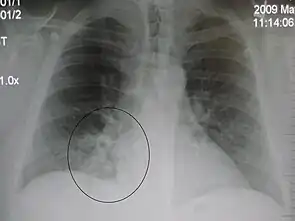

The discovery of x-rays made it possible to determine the anatomic type of pneumonia without direct examination of the lungs at autopsy and led to the development of a radiological classification. Early investigators distinguished between typical lobar pneumonia and atypical (e.g. Chlamydophila) or viral pneumonia using the location, distribution, and appearance of the opacities they saw on chest x-rays. Certain x-ray findings can be used to help predict the course of illness, although it is not possible to clearly determine the microbiologic cause of a pneumonia with x-rays alone.

AP CXR showing left lower lobe pneumonia associated with a small left sided pleural effusion

AP CXR showing right lower lobe pneumonia

AP CXR showing pneumonia of the lingula of the left lung

Right upper lobe pneumonia as marked by the circle.

Left upper lobe pneumonia with a small pleural effusion.

Right lower lobe pneumonia as seen on a lateral CXR